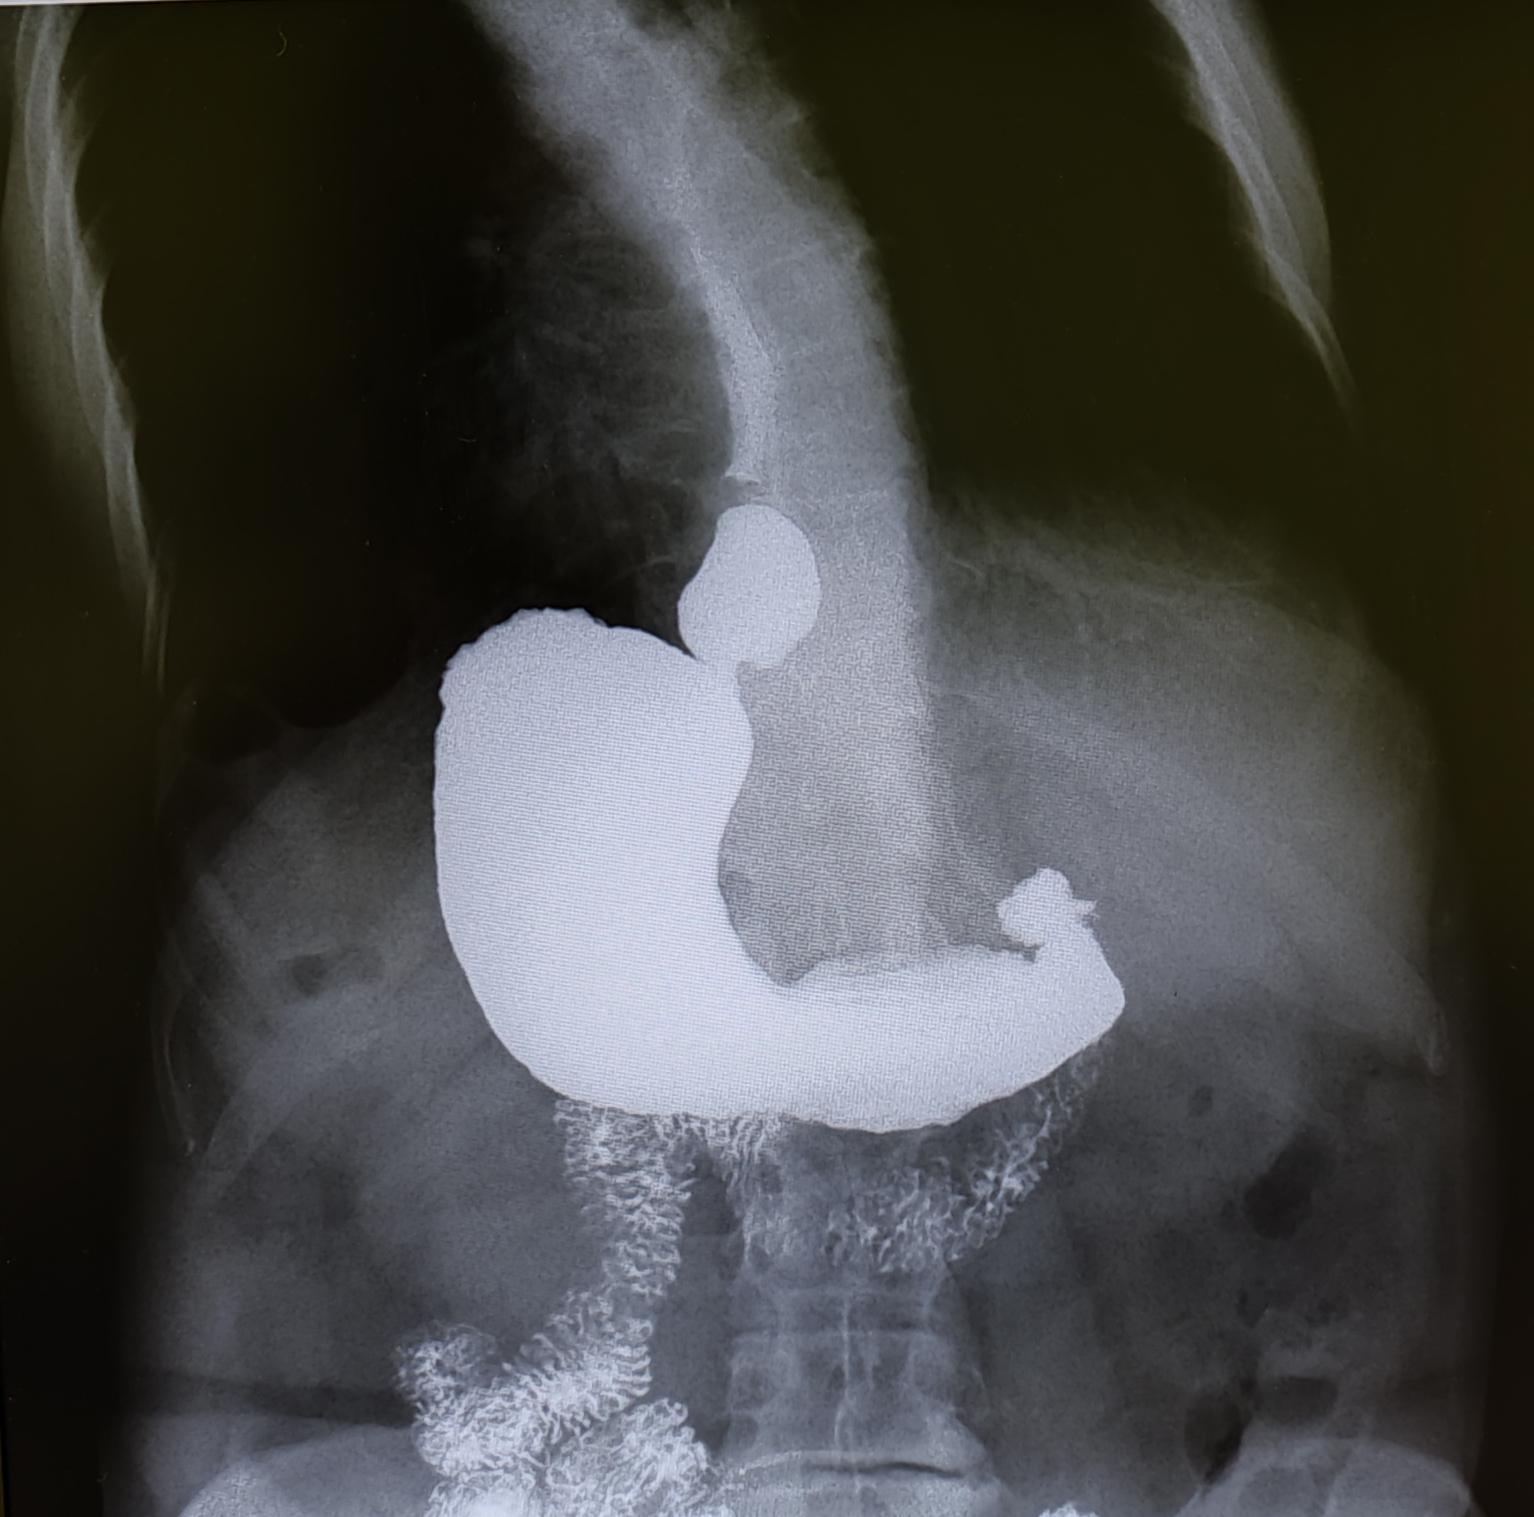

Диагностика ГПОД:ФГДС, МРТ ОБП, Рентгеноскопия желудка(для определения степени ГПОД-выполняется Р-скопия желудка в положении Тренделенбурга).

Описание: на рентгеноскопии желудка положении Тренделенбурга -над диафрагмой находится мешковидно расширенный брюшной сегмент пищевода, кардия расположена на уровне диафрагмы. Заключение: ГПОД 1ст

По 565 постановлению, I ст. ГПОД- над диафрагмой находится брюшной сегмент пищевода, кардия расположена на уровне диафрагмы.